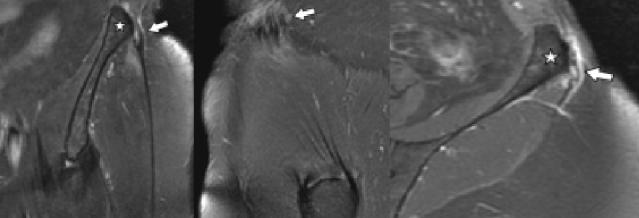

The overuse injuries in the hip joint occur commonly in sports practitioners and currently due to technical advances in diagnostic imaging, especially magnetic resonance imaging (MRI), are often misdiagnosed. Recently, a group of people were reported, all female, with pain and swelling in the pelvic region. T2-weighted MRI showed increased signal in the enthesis of the iliotibial band (ITB) along the lower border of the iliac tubercle. We report a case of a 34 year old woman, non-professional runner, with pain at the iliac crest with no history of trauma and whose MRI was compatible with the proximal iliotibial band syndrome.